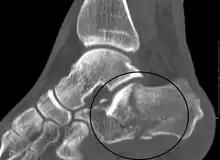

Calcaneal fracture

| X-ray of a fractured calcaneus | |

A calcaneal fracture is a break of the calcaneus (heel bone).[1] Symptoms may include pain, bruising, trouble walking, and deformity of the heel.[1] It may be associated with breaks of the hip or back.[1]

It usually occurs when a person lands on their feet following a fall from a height or during a motor vehicle collision.[2][1] Diagnosis is suspected based on symptoms and confirmed by X-rays or CT scanning.[1]